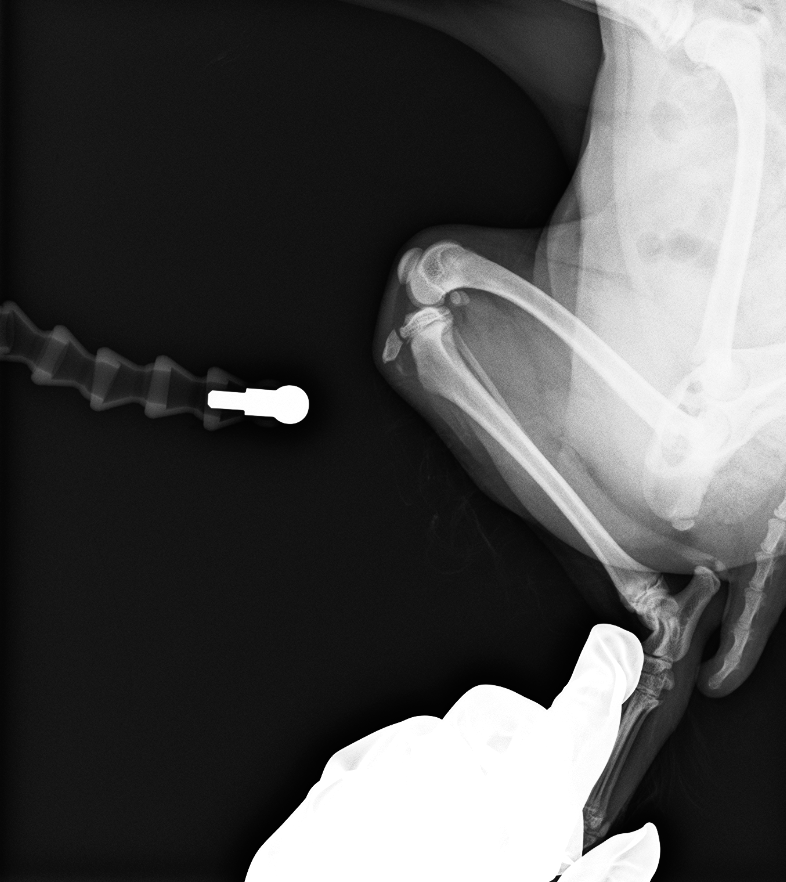

脛骨粗面にKワイヤーを挿入して固定

after